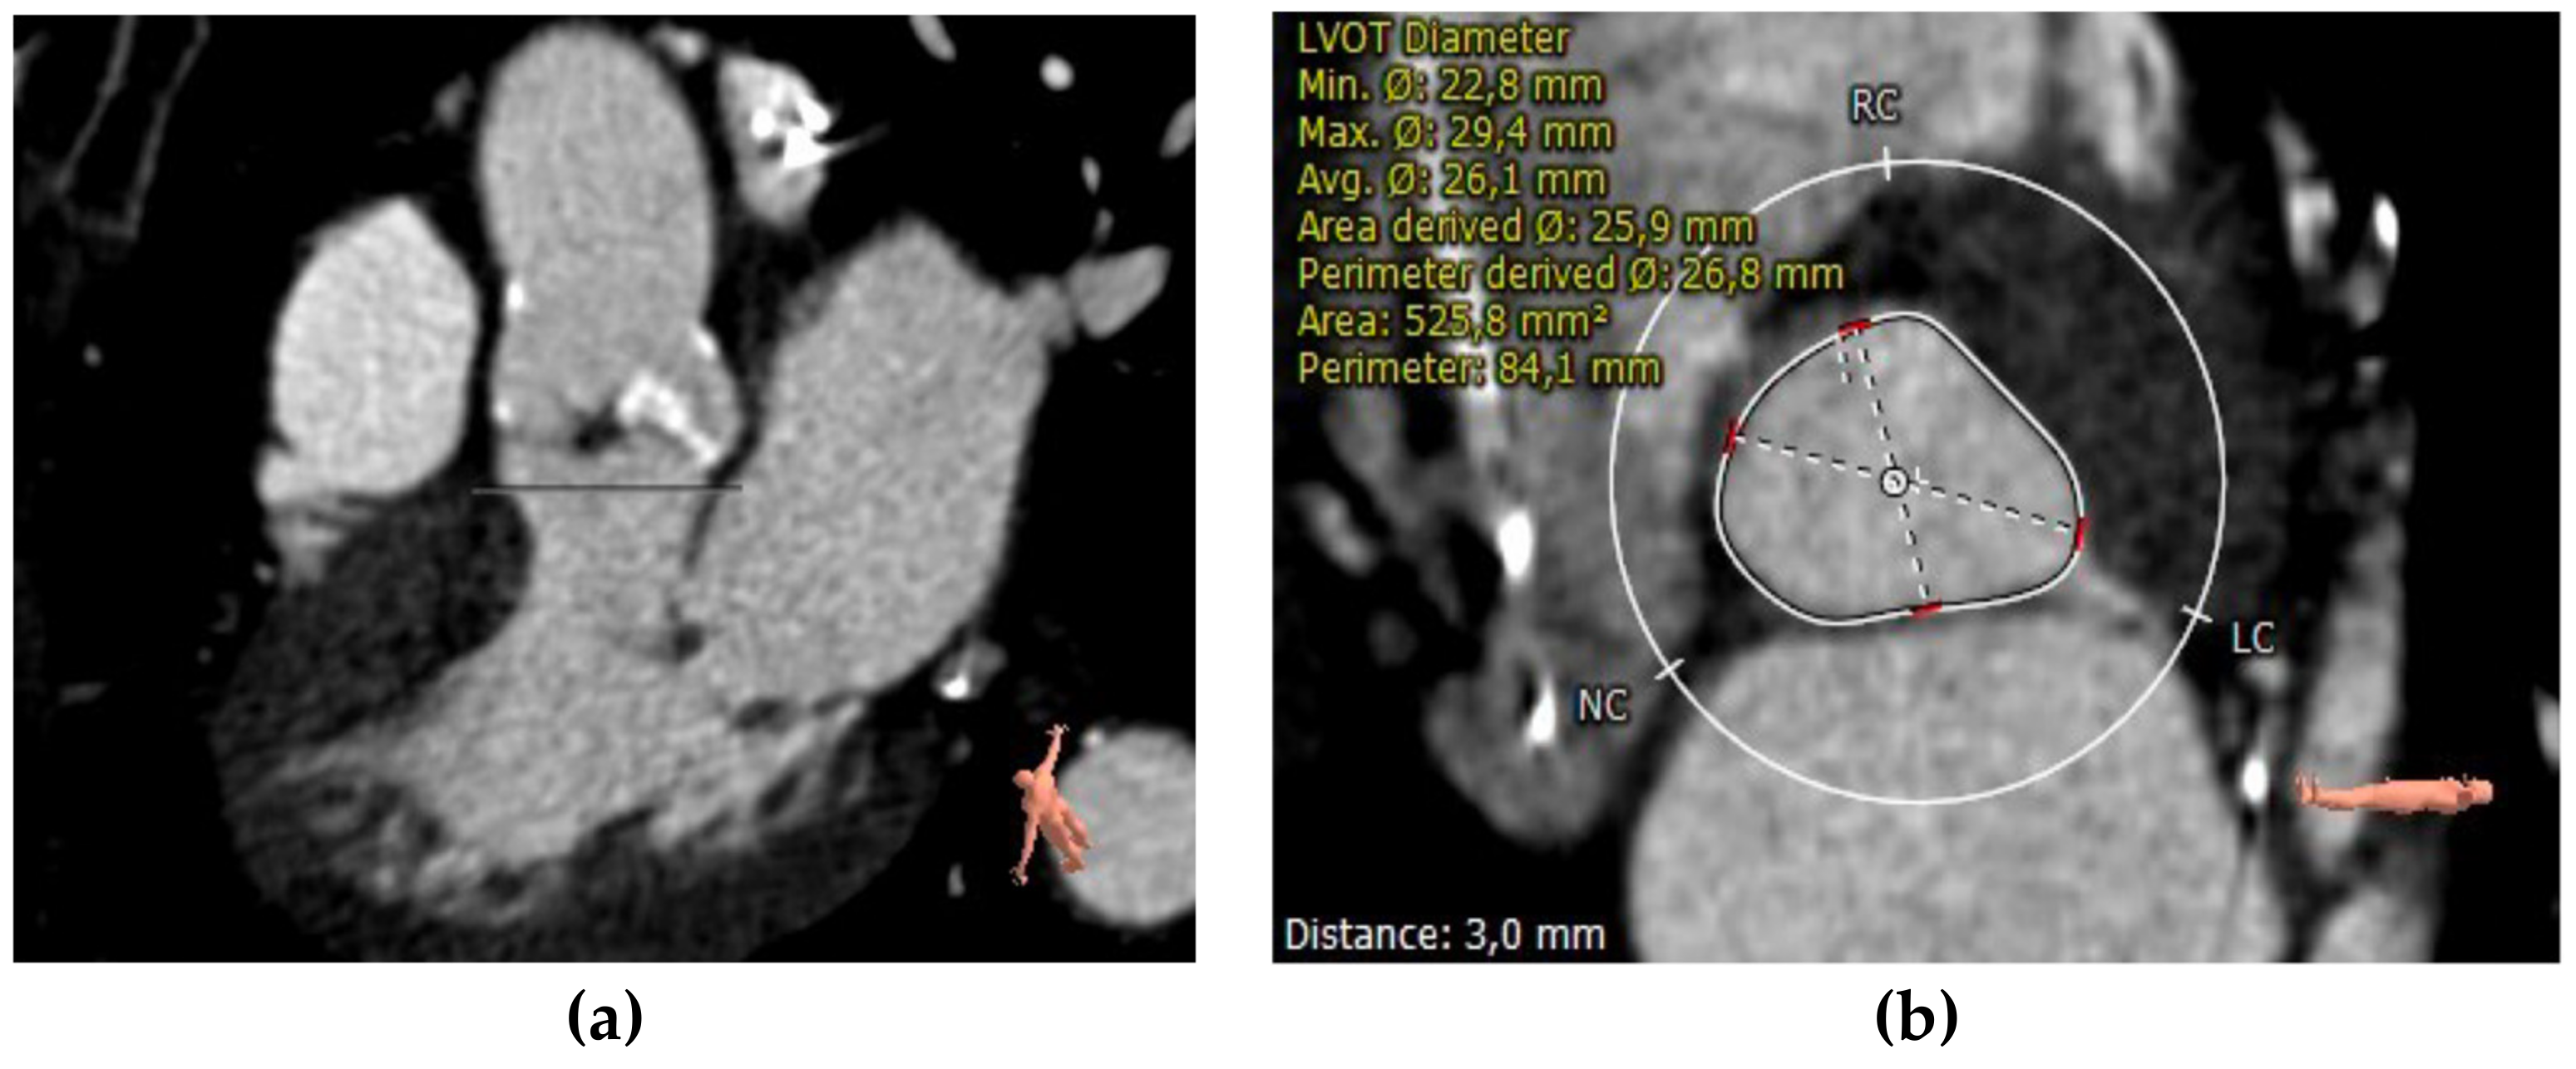

2.3.2. Aortic Annulus

The aortic annulus for implanting percutaneous prostheses is not directly visible. It is a virtual ring that passes over a plane via the basal insertions (nadir) of the aortic valve cusps. It has an oval shape that varies during the cardiac cycle, even in patients with severe calcific AS. While the size of the aortic annulus was initially determined almost exclusively via two-dimensional transesophageal echocardiography (TEE), it has been proven that the aortic annulus is a dynamic measure during the cardiac cycle. Thus, 2D imaging could not be precise enough, and only 3D imaging can display a correct measurement. Furthermore, compared with a two-dimensional assessment of the annulus, MDCT-based measures have been proven to be highly reproducible and provide a deeper understanding of annular geometry [35]. Jurenkak et al. found that, during the cardiac cycle, the aortic root varies its shape, suggesting that an MDCT evaluation during the early systole phase is the best choice for TAVI planning [36].

Annular dimension can be quantified with multiple methods: cubic spline interpolation, polygon, attenuation/Hounsfield-unit-based contour detection, and freehand contour. ECG-synchronized, ideally multiphasic, dataset should be used for proper measurement, identifying the reconstruction phase with the largest annular dimensions, thus ensuring accurate device sizing [24]. MDCT sizes the aortic annulus using annular area and perimeter measurements. In the Pivotal Trial of Medtronic Corevalve and the PARTNER 3 trial, it was demonstrated that annulus sizing based on CT measurements reduces the risk of complications such as paravalvular leakages. Moreover, the aortic annulus perimeter or cross-sectional area is superior to the annulus diameter for reducing the likelihood of paravalvular aortic regurgitation (PAR) [37,38] (Figure 3).

Figure 3.

CT measurements of perimeter and area of aortic annulus.

Another goal of current CT sizing algorithms is to calculate a certain degree of oversizing of the transcatheter heart valve (THV) to avoid the post-implantation occurrence of paravalvular leaks (PVLs). It depends on the type of THV and the measurement used (perimeter/area). Self-expandable devices need more oversizing than balloon-expandable prostheses. Conversely, severe oversizing using balloon-expandable devices might increase the annular damage. Additionally, a 10 per cent perimeter oversize does not equal a 10 per cent area oversize, but it is closer to 20 per cent [39].